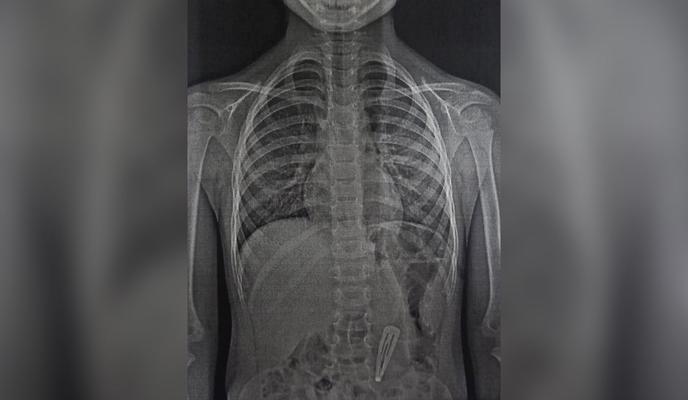

В Новороссийске в приемное отделение первой городской больницы с жалобами на боли в животе поступила 4-летняя девочка. Со слов матери ребенка врачи поняли, что причиной недомогания может быть инородный предмет в желудке. Рентгенография подтвердила эту версию.

«После этого специалисты аккуратно извлекли заколку из желудка, предотвратив ее попадание в кишечник, где она могла застрять. Тогда вытащить предмет без обширной полостной операции было бы невозможно», - рассказали в пресс-службе минздрава Кубани.